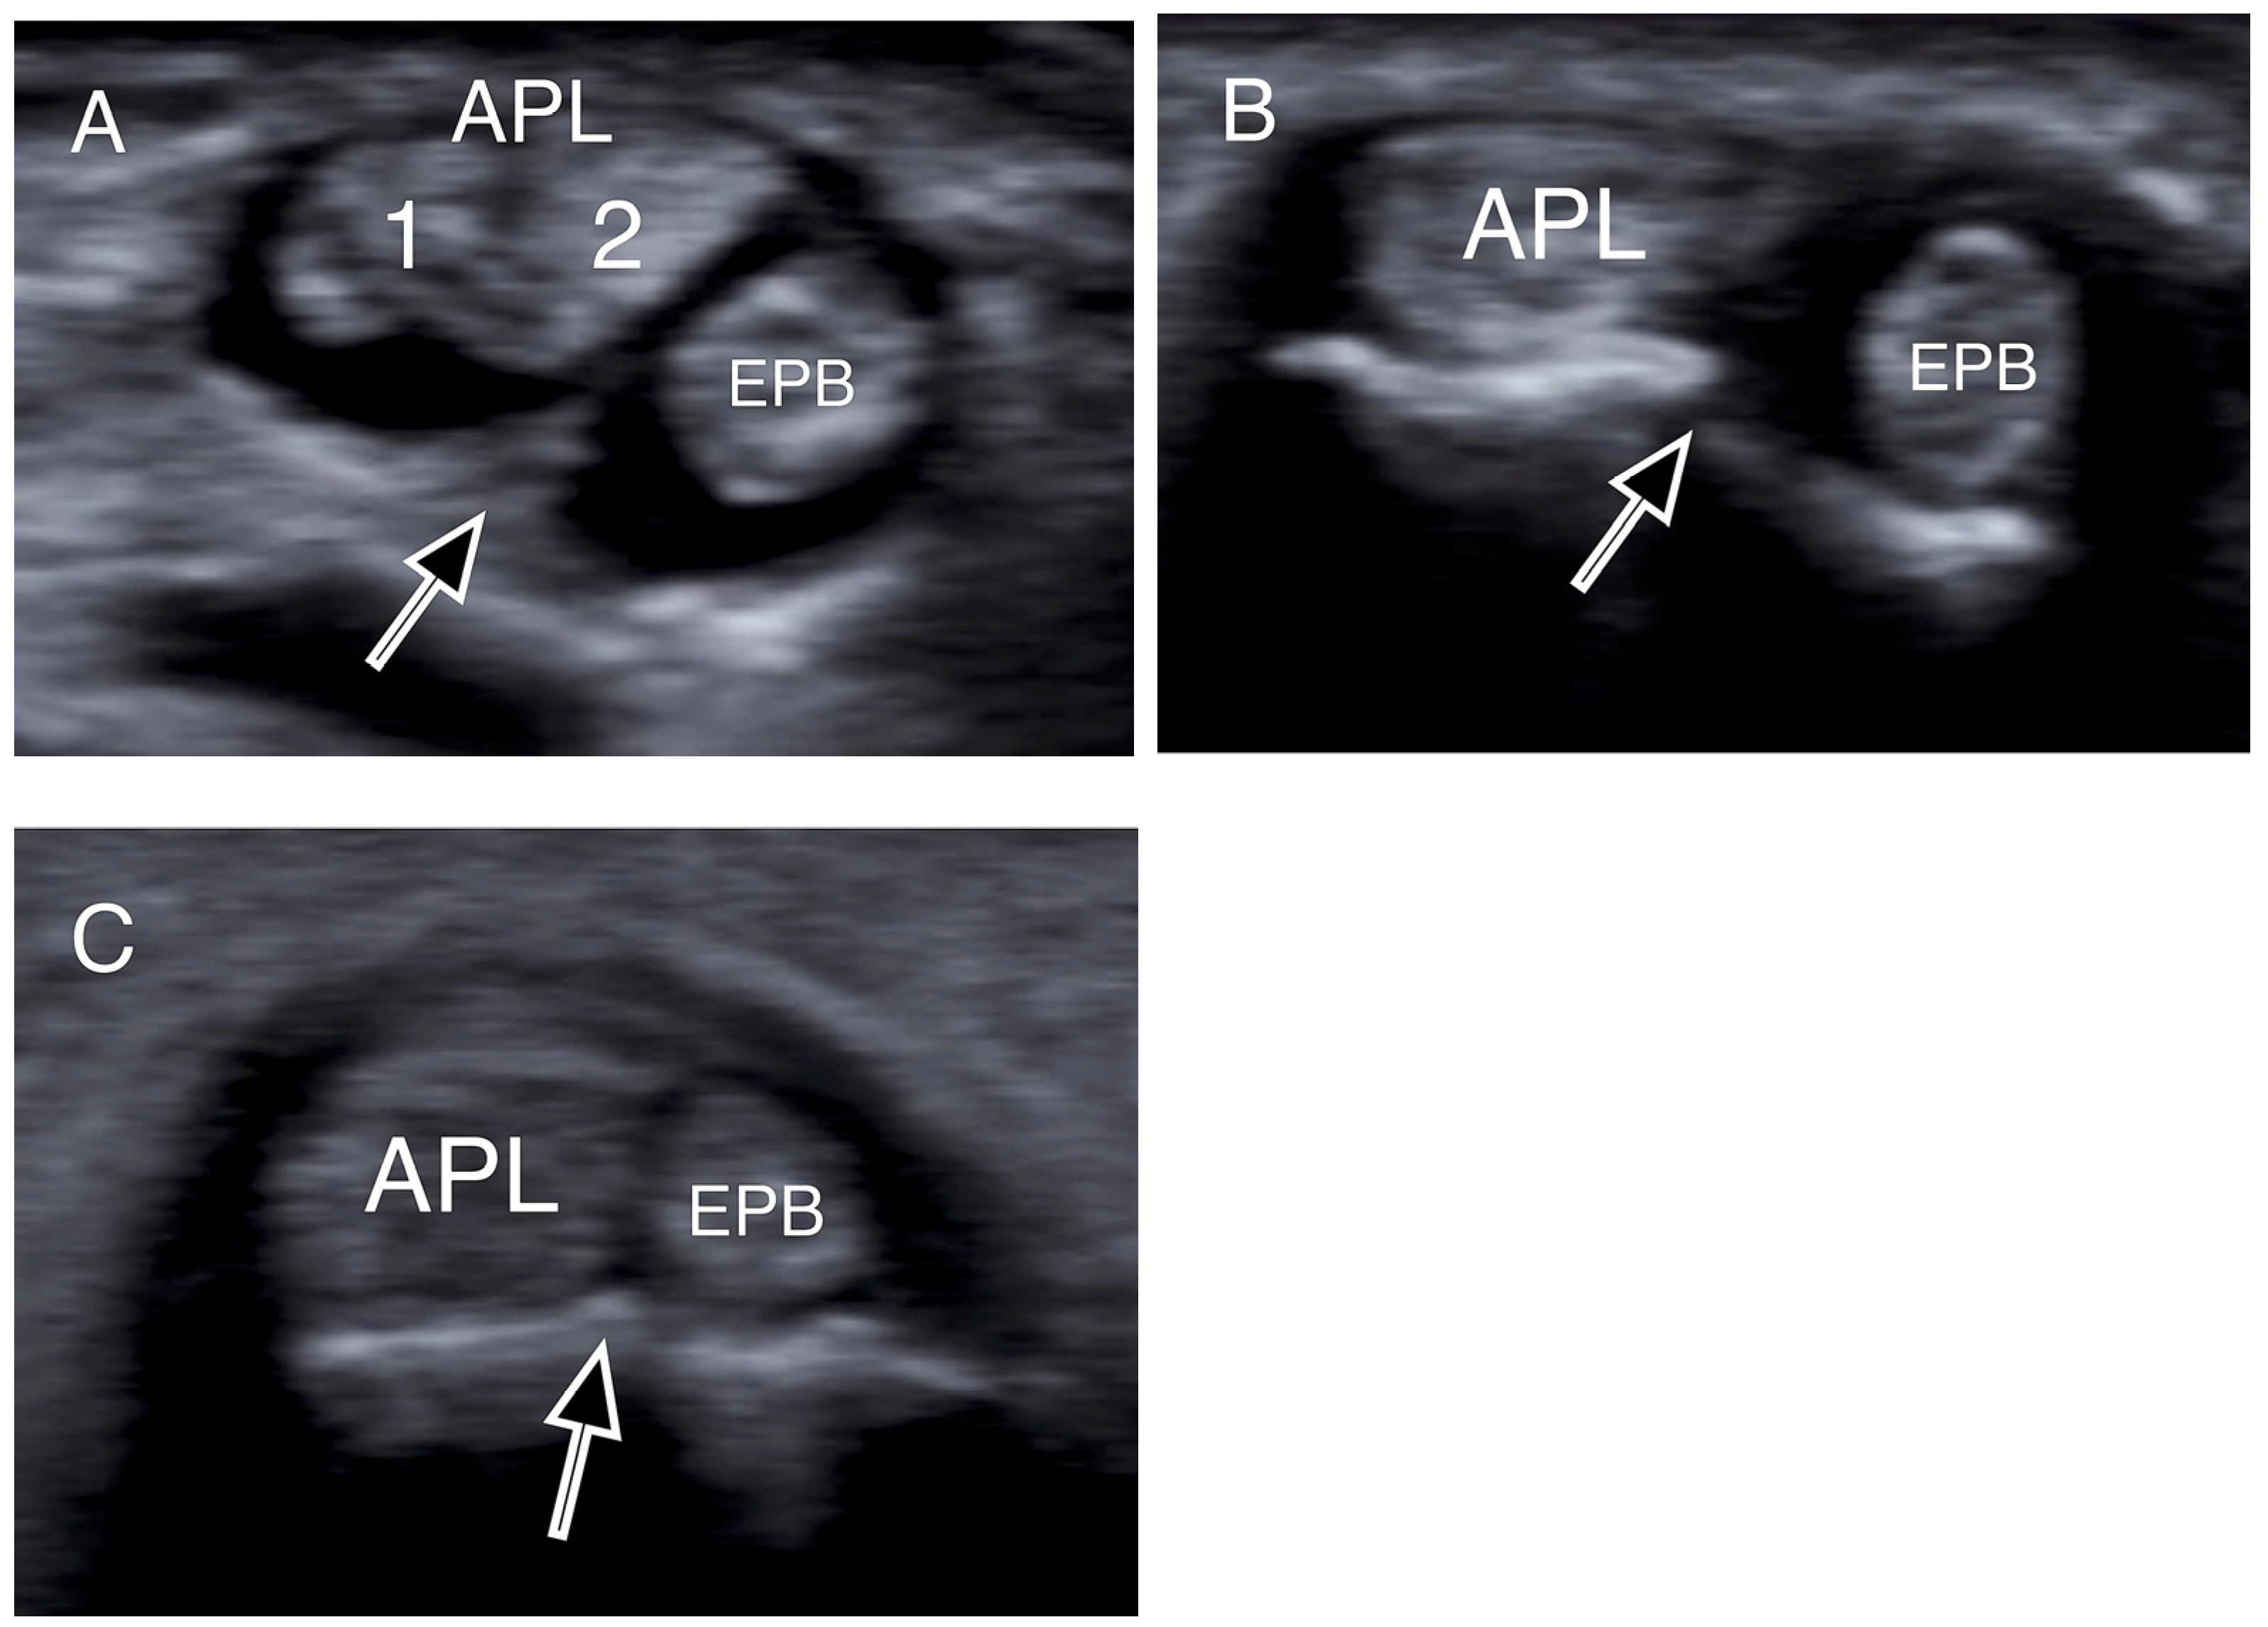

- Choi, S.J.; Ahn, J.H.; Lee, Y.J.; Ryu, D.S.; Lee, J.H.; Jung, S.M.; Park, M.S.; Lee, K.W. De Quervain Disease: US Identification of Anatomic Variations in the First Extensor Compartment with an Emphasis on Subcompartmentalization. Radiology 2011, 260, 480–486. [Google Scholar] [CrossRef]

- Kwon, B.C.; Choi, S.J.; Koh, S.H.; Shin, D.J.; Baek, G.H. Sonographic Identification of the Intracompartmental Septum in de Quervain’s Disease. Clin. Orthop. Relat. Res. 2010, 468, 2129–2134. [Google Scholar] [CrossRef]

- Abi-Rafeh, J.; Mojtahed Jaberi, M.; Kazan, R.; Alabdulkarim, A.; Boily, M.; Thibaudeau, S. Utility of Ultrasonography and Significance of Surgical Anatomy in the Management of de Quervain Disease: A Systematic Review and Meta-Analysis. Plast. Reconstr. Surg. 2022, 149, 420–434. [Google Scholar] [CrossRef] [PubMed]

| APL tendon slips (mean, range) | 2 (1–4) |

| 1 APL slip | 17 (34%) |

| 2 APL slips | 16 (32%) |

| 3 APL slips | 14 (28%) |

| 4 APL slips | 3 (6%) |